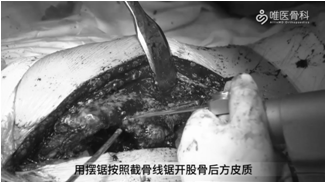

②用摆锯按照截骨线锯开股骨后方皮质,在预定平面横向分离侧方皮质。用骨刀穿透前侧皮质,并将截骨块向前方掀开,直视下清除残留骨水泥。